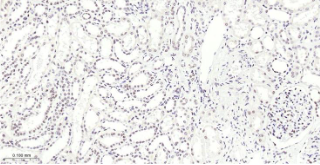

Immunohistochemical analysis of paraffin embedded human kidney tissue slide using IHC0492H (Human METTL3 IHC Kit).